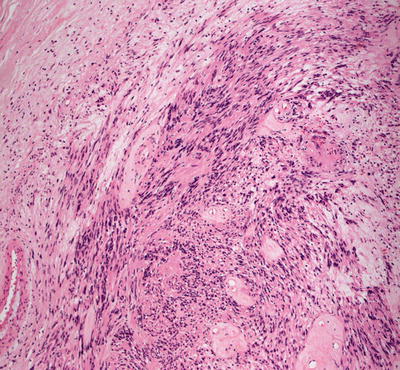

Malignant peripheral nerve sheath tumors are very uncommon in children but can arise in patients with NF1 [23, 24]. In most cases, the tumors appear to arise from within a plexiform neurofibroma. A proliferation of spindle-shaped cells with tapered nuclei and relatively scant cytoplasm is present within the dermis, growing in a fascicular and infiltrative pattern (Fig. 26.6). These tumors are markedly hypercellular with abundant pleomorphism, cytologic atypia, and mitotic activity (Fig. 26.7) [19]. Single cell necrosis and areas of zonal necrosis help to identify this as a malignant neoplasm.

Fig. 26.6

Malignant peripheral nerve sheath tumor demonstrates sheets of wavy cells coursing in fascicles